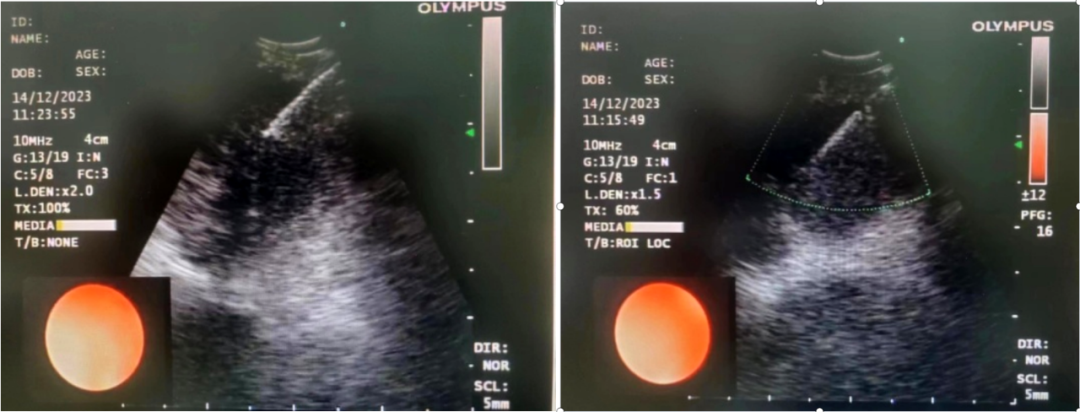

患者,女,72岁,2月来“反复咳嗽、咳痰,偶咳白痰中带血丝”,胸部CT提示“肺占位、肺炎”,收住院。完善胸部强化CT提示“左肺占位、肺炎、纵膈多发淋巴结肿大”,电子支气管镜检查见左肺上叶支气管血块及坏死物阻塞,清除后见管腔通畅,刷检DNA细胞学示“细胞退变明显,建议进一步检查”。10月27日行CT引导下肺穿刺活检,病理示“机化性肺炎”,给予抗感染及激素治疗,患者症状好转出院。半月前,患者复查肺CT发现病灶较前稍有增大,张强主任考虑患者症状虽有好转,但仍存在肿瘤性病变可能性。经过讨论及与患者家属充分沟通后,决定实施支气管内超声引导下针吸活检术(EBUS-TBNA)+电子支气管镜检查+现场快速评价(ROSE)技术,以提高诊断阳性率。术中ROSE提示查找到可疑癌细胞,取材量较足分。最后病理检查明确诊断为低分化肺腺癌,随后进行基因检测,明确了治疗方向。

患者,男,70岁,近2个月来“活动后呼吸困难,近日又出现痰中带鲜血”,收住院。胸部增强CT见“左肺下叶外周型占位,肺门、纵膈淋巴结肿大”。张强主任带领团队讨论分析患者病情,高度怀疑为肿瘤性病变,且普通电子支气管镜获取组织困难,病变紧贴主动脉,经皮肺穿刺活检风险大。为明确诊断及分期,决定为患者实施支气管内超声引导下针吸活检术(EBUS-TBNA)+电子支气管镜下病灶活检+现场快速评价(ROSE)。术中ROSE快速诊断查找到肺腺癌细胞,手术过程顺利。最后病理检查明确诊断为肺腺癌,为患者的下一步治疗确定了方向。